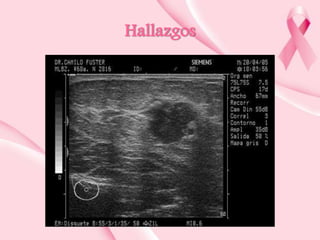

Hallazgos en técnicas de imagen

•

Nódulo redondeado u ovalado

Márgenes circunscritos

Interface abrupta

Suele ser hipoecoico y homogéneo

Puede ser isoecoico o hiperecoico

Puede mostrar estructura heterogénea

Leve refuerzo acústico posterior

Si contiene calcificaciones groseras produce sombra acústica

Tienen una orientación paralela al plano cutáneo